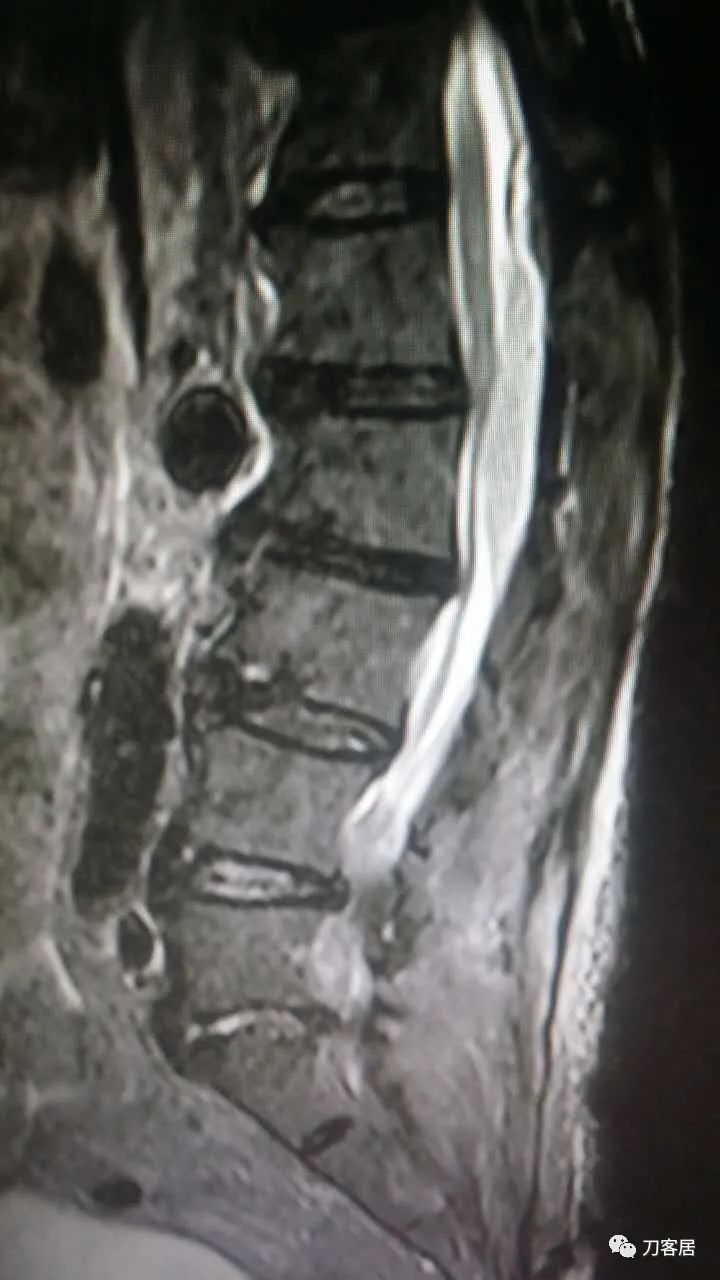

加注图5. 2015年8月17日术后5天,复查腰椎MRI提示术后改变,此平面图现在看,似乎在腰1-3椎管后方有异常信号改变,但当时手机上看,咨询我的时候,我并没有看出来,这是在电脑上操作,放大图看,似乎这里还是有问题的,但腰4-5,腰5骶1平面,椎管内信号紊乱,应该是手术后的正常表现。

这没啥问题啊(注: 上面的一张腰椎MRI T2像,现在电脑上看,似乎在腰1-3椎管后方有梭形占位病变,但当时用手机,并没有看出来。)

加注图10: 腰1-2椎管内后方可见梭形占位信号改变。

加注图11. 腰1-2椎管内后方可见梭形占位信号改变。

好像是,上面有血肿。